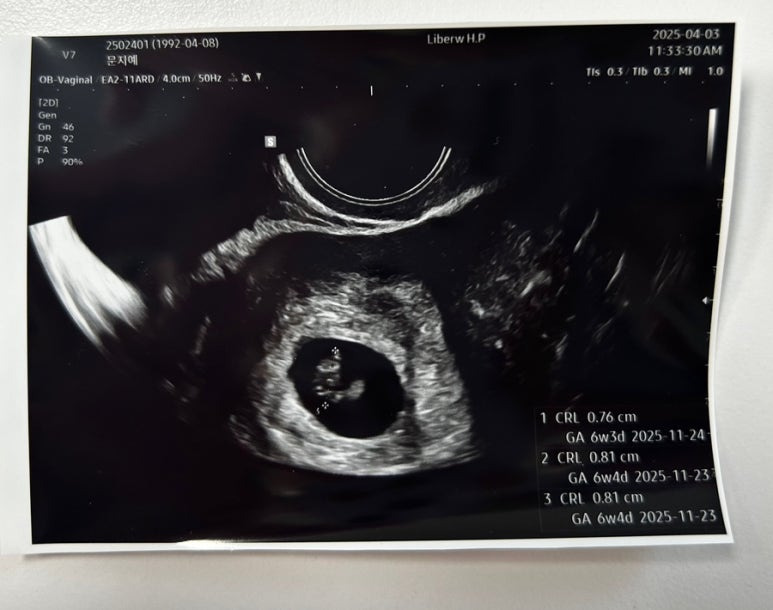

2일만에 쑥쑥커서 0.76cm가 된 사탕이🍬

장비가 좋아서 그런지 초음파가 엄청 선명하다!

드디어 6주 !!!!

예정일은 11월 24일로 변경

차뇨리랑 같이 들은 사탕이 심장소리

튼튼하게 잘 뛰고 있었다

심장박동수는 136bpm

많이 커진 난황 👼🏻